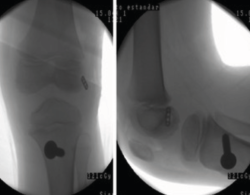

Shelbourne et al.(76) publicaron buenos resultados en 16 pacientes tratados con autoinjerto rotuliano con técnica transfisaria tibial y femoral, sin encontrar casos de deformidad ni de discrepancia de la longitud de los miembros (Figura 7).

Figura 7. Esquema de la técnica transfisaria.

Liddle et al.(77) presentaron una serie de 17 pacientes en estadio I y II Tanner intervenidos utilizando autoinjerto de isquiotibiales de 4 fascículos y atravesando ambas fisis. Todos tuvieron buenos o excelentes resultados en la escala del International Knee Documentation Committee (IKDC), sin dismetrías remarcables. Únicamente, un paciente desarrolló una deformidad leve en valgo de la rodilla, sin repercusiones funcionales.

Guzzanti et al.(78) observaron, en un estudio experimental, que el tamaño y la inclinación del túnel, así como la técnica de brocado, son factores que influyen en la superficie del área total fisaria transgredida y, por lo tanto, en el riesgo de daño fisario.

Para minimizar el riesgo de lesiones iatrogénicas, se recomienda seguir unos principios generales: los túneles deben ser perpendiculares al cartílago de crecimiento, el injerto sin pastilla ósea, evitar la colocación de tornillos interferenciales o pastillas óseas en el túnel y la disección perióstica cerca del anillo pericondral de Lacroix. Siguiendo estos principios, la aparición de deformidades angulares o dismetrías es excepcional.